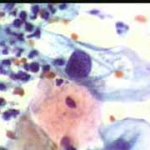

Περιστατικό ασθενούς που παρακολουθείται στο ιατρείο μας από το 1993, τότε ηλικίας 37 ετών, αρχικά λόγω ασυμπατωματικού κυτταρολογικά εμμένοντας έρπητος τραχήλου της μήτρας. Το γεγονός αυτό μας οδήγησε στην διερεύνηση της περιπτώσεως. Η ασθενής επασχε από A.I.D.S.

Είχαμε την ευκαρία να παρακολουθήσουμε ανά 6μηνο γυναικολογικά, κολποσκοιπικά και κυτταρολογικά την γυναίκα από το 1993 μεχρι και το 2008. Από τις εξετασεις αυτές, παρουσιάζουμε χαρακτηριστικές κυτταρολογικές εικόνες . Όι παρακάτω κυτταρολογικές εικονες προέρχονται από την 2η κατά σειρά εξέταση της ασθενούς το 1993. Οι κυτταρολογικές αλλοιώσεις ερπητος συνεχίζουν να υφίστανται.

Ακολουθουν κυτταρολογικές εικονες από τα έτη 1997 - 1998.